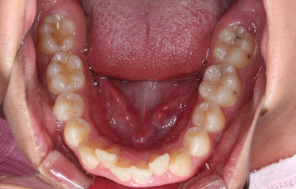

After |

After